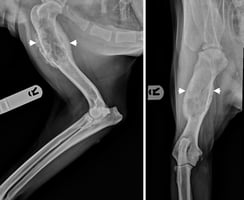

An update on diagnosis and treatment of canine appendicular osteosarcoma

Osteosarcoma (OSA) is the most common primary malignant bone tumour in dogs, comprising around 85 pe...

14 min read